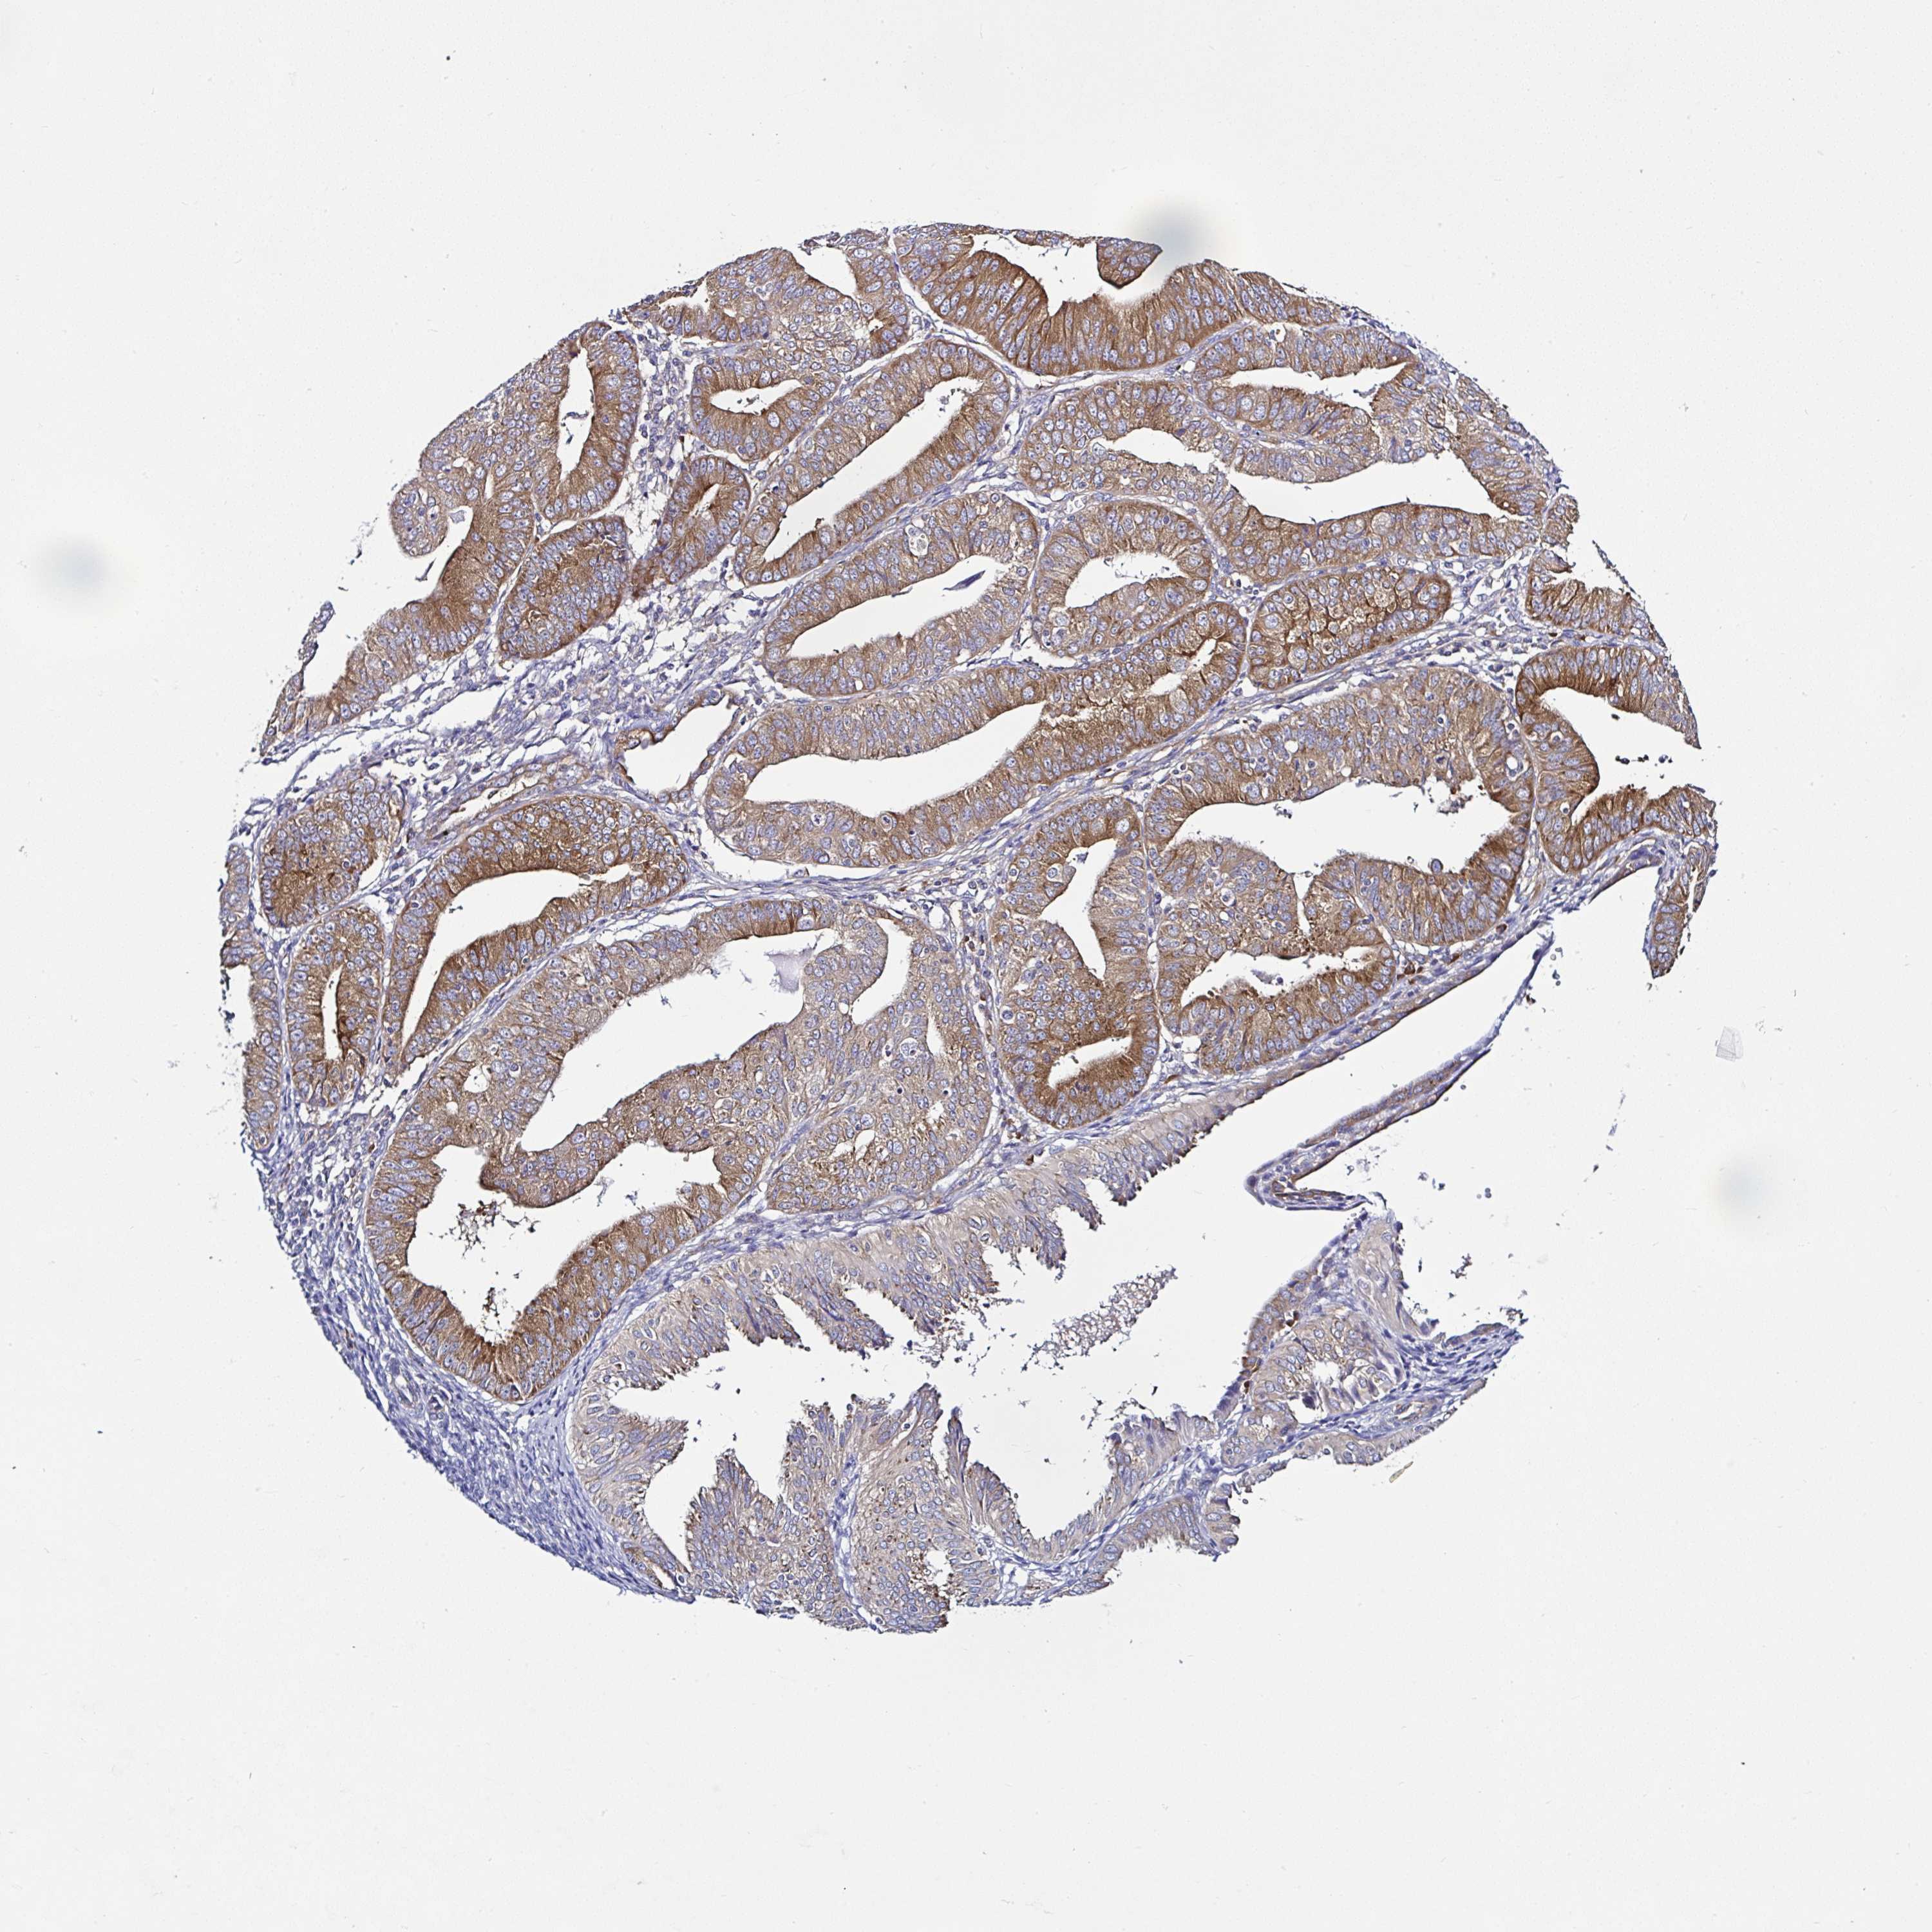

ENDOMETRIAL CANCER - Protein expressioni

A mouse-over function shows sample information and annotation data. Click on an image to view it in a full screen mode. Samples can be filtered based on level of antibody staining by selecting one or several of the following categories: high, medium, low and not detected. The assay and annotation is described here.

Note that samples used for immunohistochemistry by the Human Protein Atlas do not correspond to samples in the TCGA dataset.

Antibody stainingi

Antibody staining in the annotated cell types in the current human tissue is reported as not detected, low, medium, or high, based on conventional immunohistochemistry profiling in selected tissues. This score is based on the combination of the staining intensity and fraction of stained cells.

Each image is clickable and will lead to virtual microscopy that enables deeper exploration of all samples and also displays staining intensity scores, fraction scores and subcellular localization as well as patient and tissue information for each sample.

Antibody HPA036424

Antibody HPA040881

Staining

High

Medium

Low

Not detected

Intensity

Strong

Moderate

Weak

Negative

Quantity

>75%

75%-25%

<25%

None

Location

Nuclear

Cytoplasmic/membranous

Cytoplasmic/membranous,nuclear

Adenocarcinoma, NOS

Carcinoma, NOS

Adenocarcinoma, metastatic, NOS